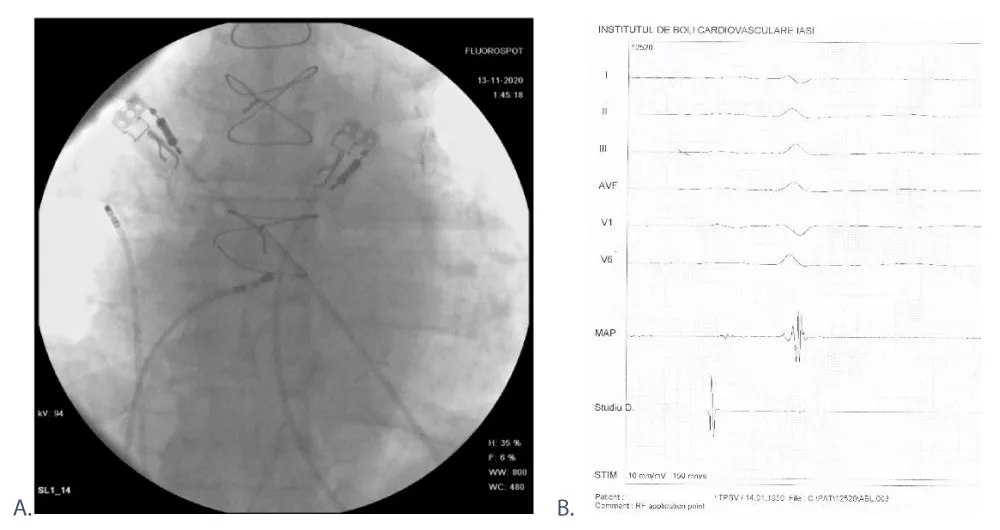

After identifying the Koch triangle elements, we localized the slow intranodal pathway anatomically – in a posterior-anterior radiological position (Figure 6A) and electrophysiologically – where the atrial deflection was small, with an atrium to ventricle ratio of 1 to 10. At this site, we performed 0:55 minutes (min) of radiofrequency applications (Figure 6B). For safety reasons, we did not reach maximal parameters of power and temperature and we frequently checked the ablation catheter position fluoroscopically, considering his AV conduction abnormalities. Post-ablation, the atrioventricular conducting parameters remained unchanged. We verify the non-inducibility of the arrhythmia using the atrial stimulation protocol by introducing up to 6 atrial extrastimuli until the nodal atrioventricular refractoriness was achieved, in basal conditions and after 1 mg of Atropine. The exposure time was 6:16 min with a radiation dose of 4995 μGy/m2 and the total procedure time was 80 min.

Download Image

Figure 6: Ablation site: A. Fluoroscopy, posterior-anterior position, showing the placement of the study catheter on the lateral wall of right atrium and ablation catheter within the Koch triangle. B. Electrogram during ablation, A to V ratio = 1:10.